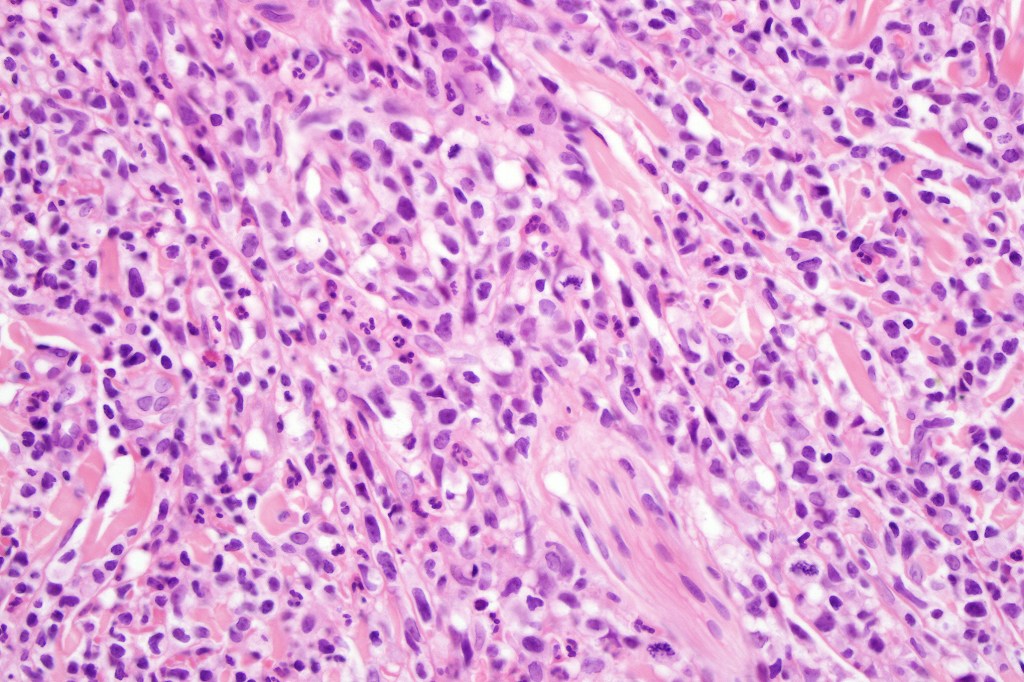

Histological features

The histological hallmark of mycosis fungoides is the presence of large atypical lymphocytes with a convoluted/cerebriform nuclear border (Sézary cells). These may be found at the epidermal-dermal jnuction and as collections within the epidermis (Pautrier microabscess). These are most easily found in plaque stage disease. The epidermal component can be subtle in patch stage disease and is often lost in tumor stage dsease. The classification into patch, plaque & tumor stage disease is less helpful histologically as the features merge from one to the other. It is all a matter of degree.

Tumor Stage Disease

•Epidermotropism is often minimal or absent

•Dense, broad diffuse or nodular, dermal infiltrate often extending into the subcutaneous fat

•Abundant Sézary cells. Frequently accompanied by very pleomorphic forms

•Mitoses often abundant, frequently abnormal

•CD30 expression correlates with transformation (cells X4 size of small lymphocytes comprising 25% or more of the infiltrate or the presence of a distinct large nodule)